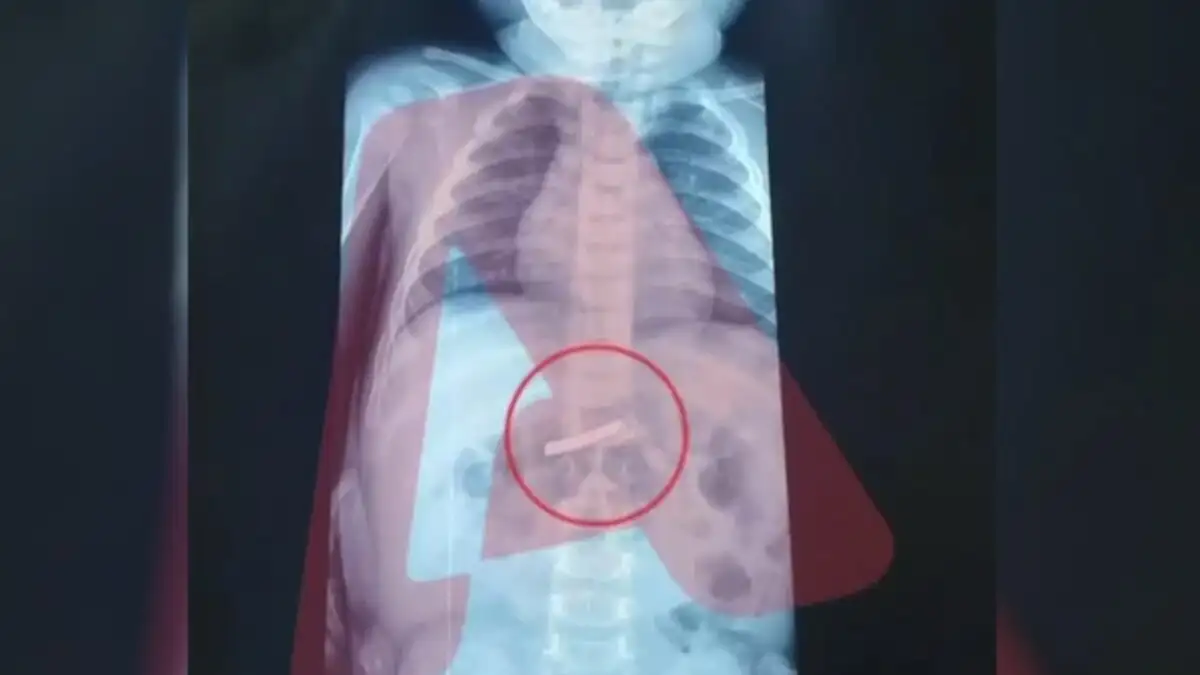

Ένας 3χρονος μεταφέρθηκε εσπευσμένα στο νοσοκομείο, το οποίο κατάπιε ένα ξυραφάκι. Το παιδί αφού έφτασε σε Παίδων της Αθήνας, υποβλήθηκε άμεσα σε ακτινογραφία, η οποία έδειξε ότι όντως υπήρχε το αιχμηρό αντικείμενο στο στομάχι του. Όπως ενημέρωσαν οι γιατροί, τους γονείς του παιδιού, μετά την ακτινογραφία προσδιορίστηκε και το ακριβές σημείο όπου βρέθηκε το ξυραφάκι, ώστε οι χειρουργοί να προχωρήσουν σε επέμβαση αφαίρεσής του με ασφάλεια. Η χειρουργική ομάδα προχώρησε άμεσα στη διαδικασία αφαίρεσης, μια επέμβαση που απαιτούσε λεπτούς χειρισμούς ώστε να αποφευχθεί οποιοσδήποτε τραυματισμός στα τοιχώματα του στομάχου ή του οισοφάγου κατά την εξαγωγή του αιχμηρού αντικειμένου. Παρά την πολυπλοκότητα και το υψηλό ρίσκο της κατάστασης, η έκβαση της επέμβασης ήταν απόλυτα επιτυχής. Οι γιατροί κατάφεραν να αφαιρέσουν το ξυραφάκι χωρίς επιπλοκές. Το μικρό αγόρι, μετά την ολοκλήρωση της διαδικασίας, μεταφέρθηκε σε θάλαμο νοσηλείας όπου και αναρρώνει πλέον υπό τη συνεχή επίβλεψη των ειδικών. Η έκβαση της επέμβασης ήταν επιτυχής και το μικρό παιδί αναρρώνει στο νοσοκομείο.

Σε ανάρτησή της η παιδίατρος Αρετή Μανιώτη δίνει στους γονείς συμβουλές για τις πρώτες βοήθειες αντιμετώπισης αυτού του δύσκολου περιστατικού. Όπως εξηγεί «Η κατάποση ξένου σώματος είναι αρκετά συχνή στις μικρές ηλικίες, όμως όταν πρόκειται για αιχμηρό αντικείμενο, όπως ένα ξυραφάκι, πρόκειται για επείγουσα κατάσταση. Το πρώτο βήμα είναι πάντα να δούμε πού βρίσκεται, με ακτινογραφία τραχήλου, θώρακα και κοιλίας. Αν είναι στον οισοφάγο, η αφαίρεση πρέπει να γίνει άμεσα με ενδοσκόπηση. Ακόμα όμως κι αν έχει φτάσει στο στομάχι, πάλι δεν το αφήνουμε στην τύχη του — λόγω του σχήματός του, συνήθως προχωράμε σε ενδοσκοπική αφαίρεση όσο πιο γρήγορα γίνεται. Αν έχει ήδη περάσει πιο κάτω στο έντερο, τότε μπαίνουμε σε στενή παρακολούθηση, με επανεκτιμήσεις και οδηγίες στους γονείς για συμπτώματα που δεν πρέπει να αγνοηθούν, όπως πόνος στην κοιλιά, εμετοί, αίμα ή πυρετός. Σημαντικό: δεν προκαλούμε εμετό και δεν δίνουμε τροφή με σκοπό να “σπρώξει” το αντικείμενο»